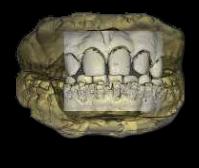

FIGURA 1 (TOMOGRAFIA VISTA FRONTAL)

RECONSTRUCCION 3D DE LA ZONA A ESTUDIAR

Las reconstrucciones tridimensionales nos permiten una visualización detallada y precisa de las estructuras vecinas a la pieza retenida, superando las limitaciones 2D de las radiografías convencionales, también ayudara en este caso para la planificación quirúrgica y posterior tratamiento de ortodoncia.

En este caso podemos observar una lesión de diámetro considerable de bordes corticalizados y forma irregular proyectada en el maxilar superior en el cuadrante 1, que se extiende desde distal de la pieza 1.1 hasta distal de la pieza 1.5, desde el tercio apical de las piezas 1.2 – 1.4 y 1.4 por vestibular y desde cervical por palatino. Se evidencia también a la pieza 1.3 retenida desplazada el ápice hacia la cortical palatina y la corona hacia la cortical palatina

CORTES AXIALES

Con la evaluación de la tomografía volumétrica en cortes axiales y transversales se observa la expansión y adelgazamiento de la tabla ósea vestibular y palatina legando a dicha pérdida ósea, también se observa el desplazamiento de la pieza 1 3 la cual se encuentra retenida y desplazada hacia la basal vestibular.

CONCLUSION

CORTES SAGITALES

A nivel de los cortes sagitales y coronal verificamos la extensión de la lesión y evidenciar el desplazamiento de las piezas 1.2 a mesial y 1.4 hacia distal a causa de la retención de la pieza 1.3 y expansión de la lesión